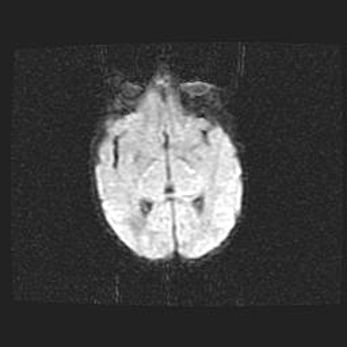

Наружная гидроцефалия с возможной атрофией височных областей.

Возраст: 28 дней

Вес: 3670 г

Пол: мужской

Окружность головы: 38 см

Срок гестации: 40 недель

Гидроцефалия головного мозга у новорожденных – это заболевание, которое характеризуется скоплением избыточного количества спинномозговой жидкости в желудочковой системе головного мозга в результате затруднения её перемещения от места выработки к месту поглощения в кровеносную систему или вследствие нарушения абсорбции. При открытой наружной форме гидроцефалии у новорожденных расширяются и переполняются субарахноидные пространства.

При нормотензивных  формах,  которые,  как  правило,  являются  следствием  перенесенных ишемических  повреждений  паренхимы  мозга,  возможно  сочетание микроцефалии  с нормотензивной гидроцефалией. В основе данных изменений лежит атрофия больших полушарий с преимущественной  локализацией  в  лобно-височных  областях.